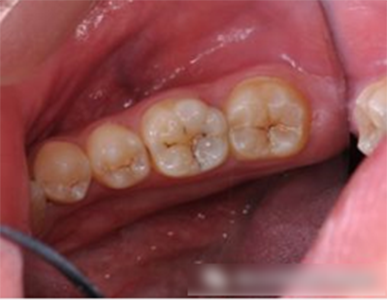

第二恒磨牙也有深的窩溝點(diǎn)隙